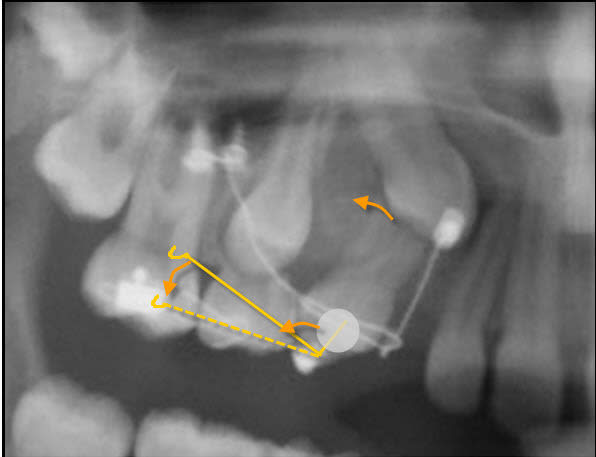

Réaliser deux danchemon sur la face vestibulaire de la 14 pour qu'un fil passant au travers puisse réaliser un couple. Jusque la ça ne change pas.

Ensuite faire passer un fil d'egiloy dans le danchemon sortant en distal (le fil se dirigera donc dans une direction apical).

Accrocher l’extrémité distal du fil d'egiloy sur la fil en TMA. La on aura :

Création d'un mouvement anti horaire sur la 14 qui nous remettra la 14 dans l'axe.

Création d'une composante vertical a direction apical sur le fil de TMA qui va supprimer la mise sous tension de la 13. Donc dancha ne vas pas vouloir de cette solution.

Donc pour modifier je fais sortir le fil d'egiloy en mesial .du danchemon avec une direction de sortie occlusal on le raccroche ensuite a la bouche du fil de TMA on aura donc

- une force en direction occlusal s'exerçant sur la boucle du fil en TMA qui maintient la force éruptive sur la canine

- une force intrusive sur la 14 mais qui sera compenser par la mise sous tension du TMA ( les minivisse s'opposant a l'expression de cette composante).

- un moment réactionnel anti horaire mettant la 14 dans l'axe